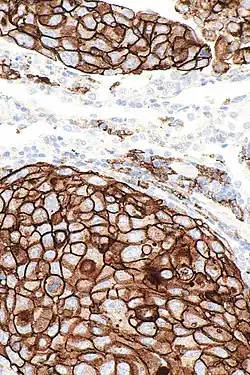

Not all patients respond to PD-1/PD-L1 inhibitors. The FDA has approved several assays to measure the level of PD-L1 expressed by tumor cells, in order to predict the likelihood of response to an inhibitor. PD-L1 levels have been found to be highly predictive of response. Higher tumor mutational burden is also predictive of response to anti-PD-1/PD-L1 agents.[8] However, these markers are far from perfect, and there is a clinical interest in the search for new biomarkers predictive of the benefit of these therapies beyond PD-L1 and TMB levels.[12][13][14]